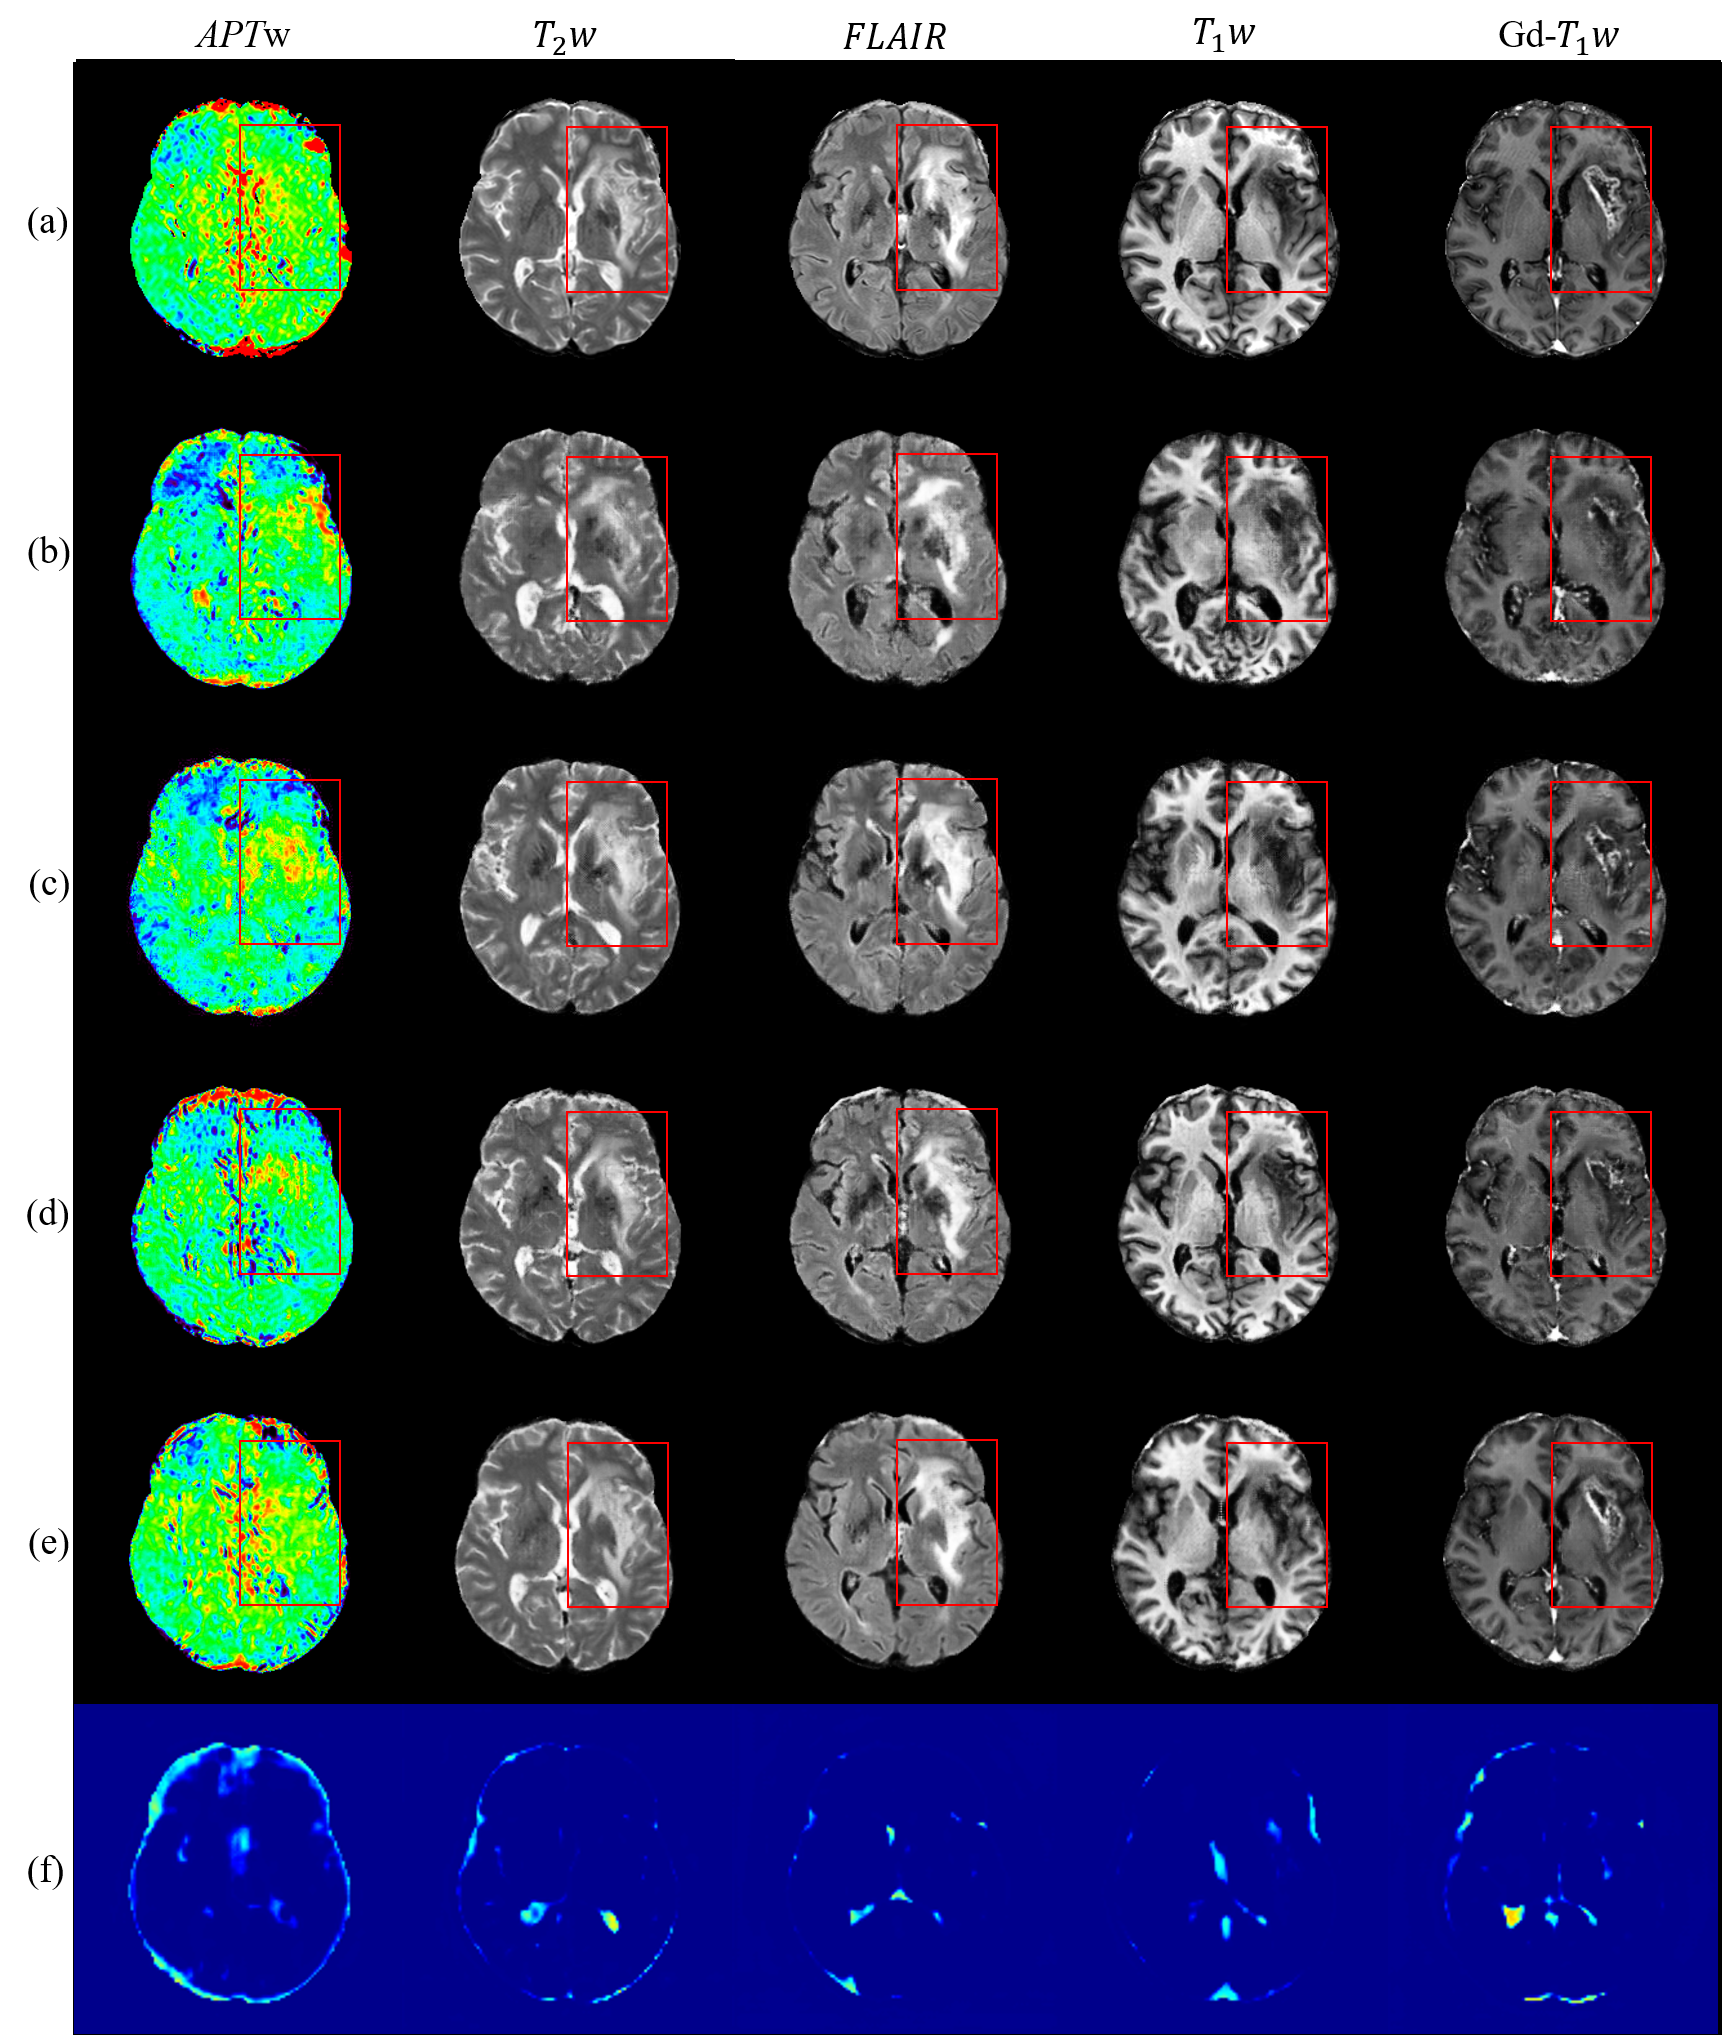

Figure 1: Sample multi-modal MR image synthesis results. (a) Ground truth. (b) Synthesis using Shin et al. [1]. (c) Synthesis using pix2pix [2]. (d) Synthesis using pix2pixHD [3]. (e) Synthesis using the proposed CG-SAMR method. (f) Confidence maps from CG-SAMR, where blue represents the most confident and red represents the least confident region.

Goodfellow et al. [11] proposed the generative adversarial networks (GAN) and first applied to synthesize photo-realistic images. Isola et al. [2] and Wang et al. [3] further investigated conditional GAN and achieved impressive solution to image-to-image translation problems. Synthesizing realistic MR images is a difficult task since radiographic features dramatically varies on MR images corresponding to underlying diverse pathological changes. Nevertheless, several generative models have been successfully proposed for MRI synthesis. Nguyen et al. [12] and Chartsias et al. [13] proposed CNN-based architectures to synthesize cross-modality MR images. Cordier et al. [14] further used a generative model for multi-modal MR images with brain tumors from a single label map. However, their inputs are conventional MRI modalities, and the diversity of the synthesized images is limited by the training images. Moreover, the method is not yet capable of producing manipulated outputs. Shin et al. [1] adopted Pix2Pix [2] to transfer brain anatomy and lesion segmentation maps to multi-modal MR images with brain tumors. Although, their approach can synthesize realistic brain anatomy for multiple MRI sequences, it does not consider significant differences of radiographic features between anatomic and molecular MRI. Moreover, pathological information are high frequency components and may need extra supervision during synthesis. As a result, their method cannot produce realistic molecular MR images and fails around the lesion region (see Figure 1(b)).

In our previous work, synthesis of anatomic and molecular MR images network (SAMR) [15], a novel generative model was proposed to simultaneously synthesize a diverse set of anatomic and molecular MR images. It takes arbitrarily manipulated lesion masks as input, which is facilitated by brain atlas generated from training data. SAMR [15] is a GAN-based approach, which consists of a stretch-out up-sampling module, a segmentation consistency module, and multi-scale label-wise discriminators. In this paper, we extend SAMR [15] by incorporating extra supervision on the latent features and their confidence information to further improve the synthetic performance. Intuitively, directly providing the estimated synthesized images (i.e. intermediate results) to the subsequent layers of the network may propagate errors to the final synthesized images. With the confidence map module, the proposed algorithm is capable to measure an uncertainty metric of the intermediate results and block the flow of incorrect estimation. To this end, we formulate a joint task of estimating the confidence score at each pixel location of intermediate results and synthesizing realistic multi-modal MR images. Figure 1(e) presents sample results from proposed network, where CG-SAMR generates realistic multi-modal brain MR images with more detailed pathological information as compared with Figure 1(b-d). Furthermore, to overcome the insufficiency of paired training data, we modify the network to allow unsupervised training, namely unpaired CG-SAMR (UCG-SAMR). In other words, the proposed unsupervised approach does not require aligned pairs of lesion segmentation maps and multi-modal MR images during training. This is achieved by adding an extra GAN which reverses the synthesis process to a segmentation task. In summary, this paper makes the following contributions:

The encoder part (orange blocks in Figure 2) consists of a fully-convolutional module with 5 layers and subsequent 3 residual learning blocks (ResBlock) [40]. We set the kernel size and stride equal to 7 and 1, respectively, for the first layer. For the purpose of down-sampling, instead of using maximum-pooling, the stride of other 4 layers is set equal to 2. Rectified Linear Unit (ReLu) activation and batch normalization are sequentially added after each layer. To learn better transformation functions and representations through a deeper perception, the depth of the encoder network is increased by 3 ResBlocks [10, 40]. We can observe the significant different radiographic features between anatomic and molecular MR images as shown in Figure 1(a), which vastly increases the difficulty of simultaneous synthesis. To address this issue, the decoder part (green blocks in Figure 2) consists of 3 ResBlocks and a stretch-out up-sampling module that contains 5 same sub-modules designed to utilize the same latent representations from the preceding ResBlock and perform customized synthesis for each MR sequence. Each sub-module contains a symmetric architecture with a fully-convolutional module in the encoder. All convolutional layers are replaced by transposed convolutional layers for up-sampling. The synthesized multi-modal MR images are produced from each sub-model.